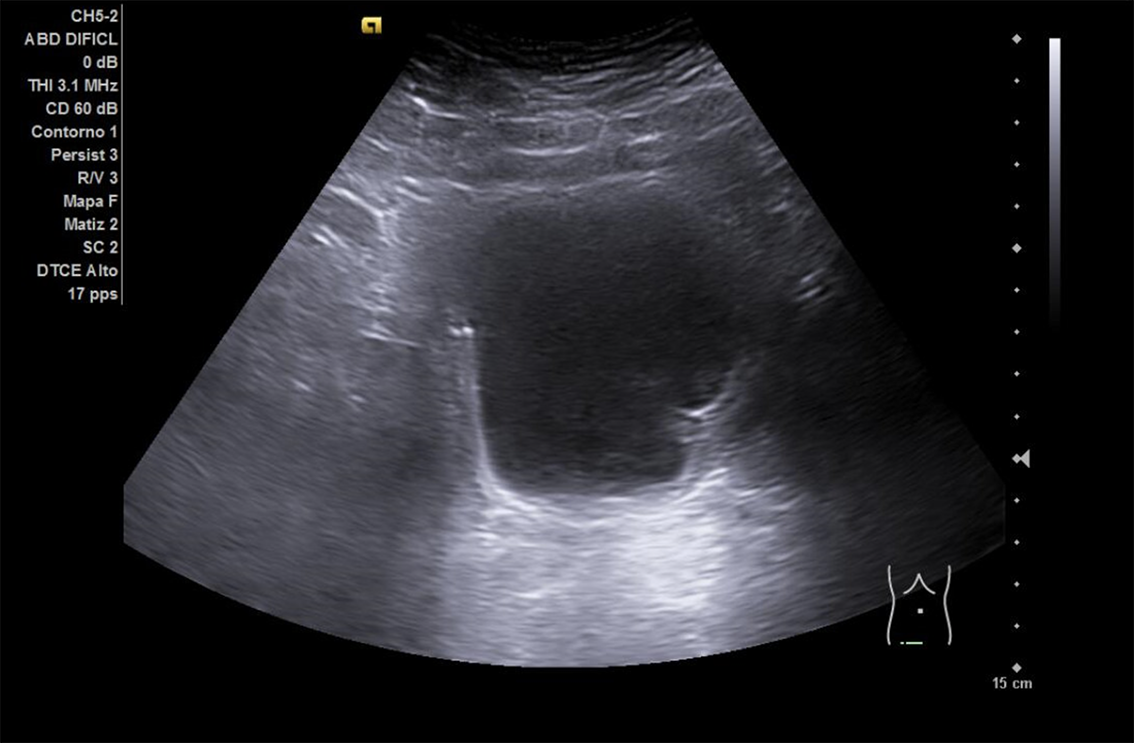

Descripción de los hallazgos ecográficos y las imágenes más relevantes para la resolución del caso

Se realiza ECO POCUS en la que se aprecia riñón derecho de morfología y tamaño normal. Riñón izquierdo con hidronefrosis grado III. A nivel de vejiga, bien replecionada se aprecia masa a nivel de pared izquierda adyacente a unión ureterovesical de 1.8 x 2,7 cm Ausencia de jet izquierdo.